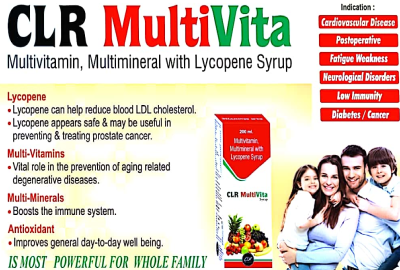

CLR-pharmaceutical is an certified company. it is considered to be one of the fastest growing Pharmaceuticals company. We have a dedicated team of technical professionals with extensive experience in Pharmaceuticals industry who are committed to produce various formulations with stringent quality standards, keeping in mind the social responsibility to contribute better health care of the society. All our manufacture are WHO certified companies in Pharma & FSSAI & ISO registered companies in Nutritional products. Our products are high quality products with beautiful packing manufactured under strict quality control as per schedule M –GMP guideline. The formulation objective of our company is to provide scientifically sound quality product and solution to cure disease and improve the quality of life.